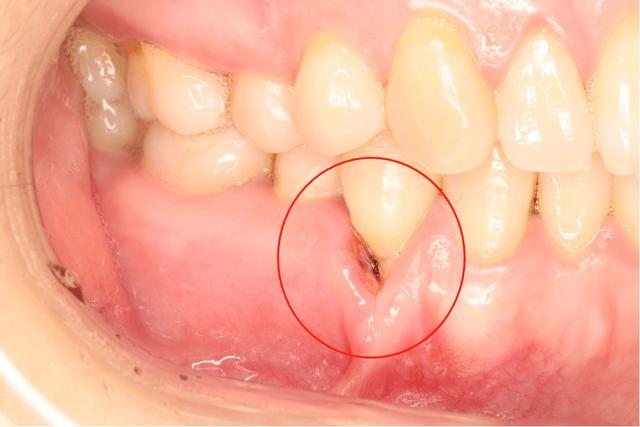

牙周炎的癥狀

1、牙齦紅腫:牙周炎患者的牙齦組織通常會變得紅腫。

2、牙齦出血:刷牙或咬硬物時容易出血。

5、牙齒松動:炎癥嚴(yán)重時,可能導(dǎo)致牙齒松動。